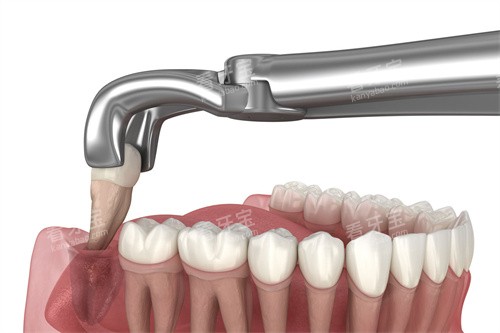

拔牙那天,我紧张得手心直冒汗。医生先给我打了麻药,说实话针扎进去的瞬间确实有点疼,但很快就麻木了。整个拔牙过程比我想象的快,大概就十几分钟。